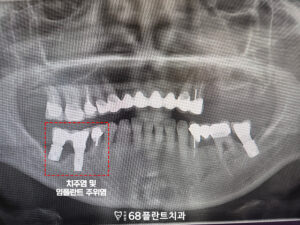

그리고 아래쪽도 잇몸뼈가 부족하고

예후가 불량했던 부위를 전부 발치한 뒤,

임플란트를 식립하여

기능적인 회복을 도모했습니다.

발치 후에는 뼈 이식을 통해

잇몸뼈의 소실된 부분을 보충하고,

이를 바탕으로 임플란트를

안정적으로 식립할 수 있도록 했습니다.

이렇게 임플란트를 식립함으로써

잇몸뼈가 부족했던 부위도

다시 기능을 회복할 수 있었고,

전체적인 치료의 안정성과

장기적인 유지 가능성을

높일 수 있었습니다.

그리고 아래쪽도

임플란트의 치유기간을 거친 뒤

최종 보철 작업 후 마무리 하였습니다.